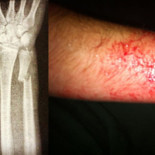

Recibe tres puñaladas y entra a un bar a pedir una cerveza

Un individuo de unos 35 años recibió ayer en Castellón tres puñaladas en el pecho y no se le ocurrió otra cosa que entrar en un bar a pedir una cerveza.